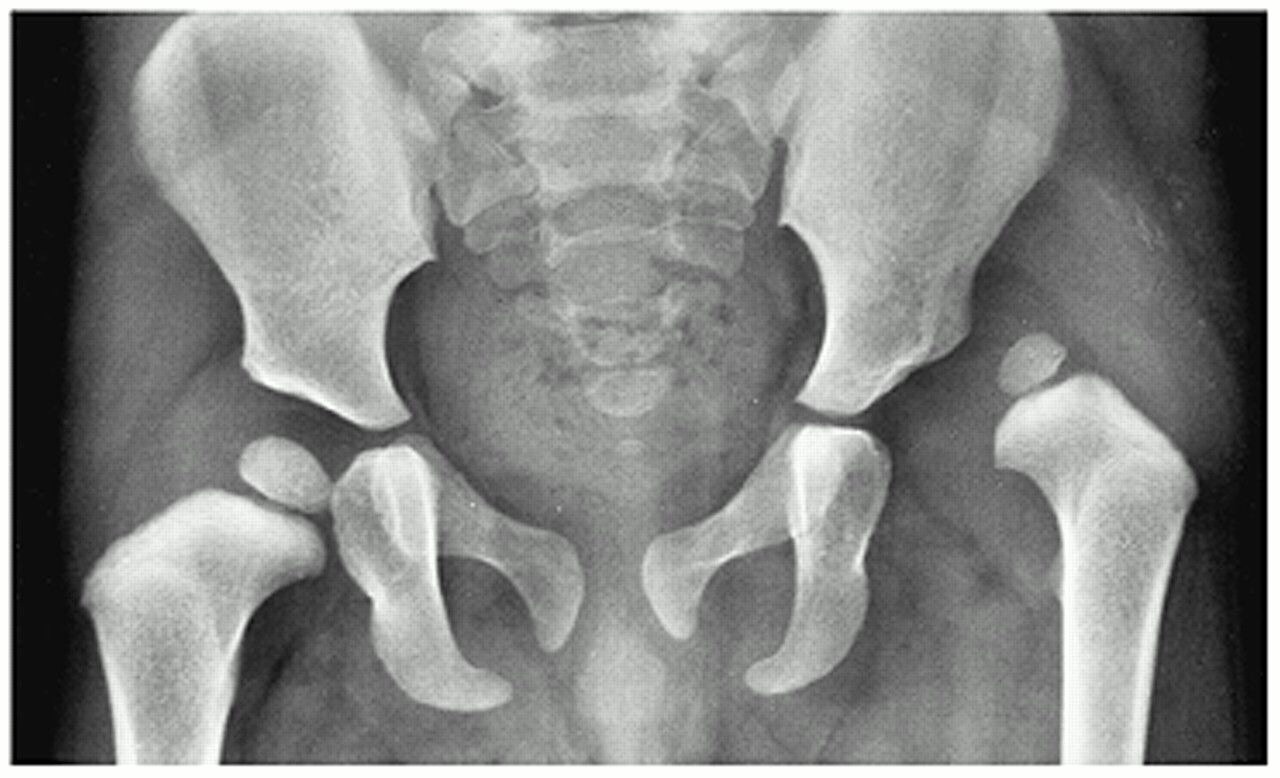

Gelişimsel Kalça Displazisi (GKD)

Kalça displazisi ya da çıkığının bir ortopedist tarafından özenli bir muayene sonucunda olabildiğince erken teşhis edilmesi çok önemlidir. Bu muayenede kalçanın hareket yeteneği ölçülür. Kabaca bebek tek taraflı ya da çift taraflı olarak bacaklarını ayırmakta zorlanıyorsa ve poposundaki kıvrımlarda asimetri varsa, kalça ekleminde bir sorun olduğundan şüphelenilebilir. Ancak fizik muayene ile tüm vakaların yakalanması her zaman mümkün olmayabilir. Asıl önemli olan kalça muayenesi normal olan ancak displazisi bulunan kalçaların erken teşhis edilebilmesidir.

Dünya Sağlık Örgütü ve Türk Pediatrik Ortopedi Derneği’nin tedavi algoritmasına göre her bebeğin doğumundan sonra birinci, ikinci ve üçüncü aylarında kalça ultrasonunun yapılması ve 6. ayda ise kalça grafisinin çekilmesi ve mutlaka bir ortopedist tarafından görülmesi gerekmektedir.